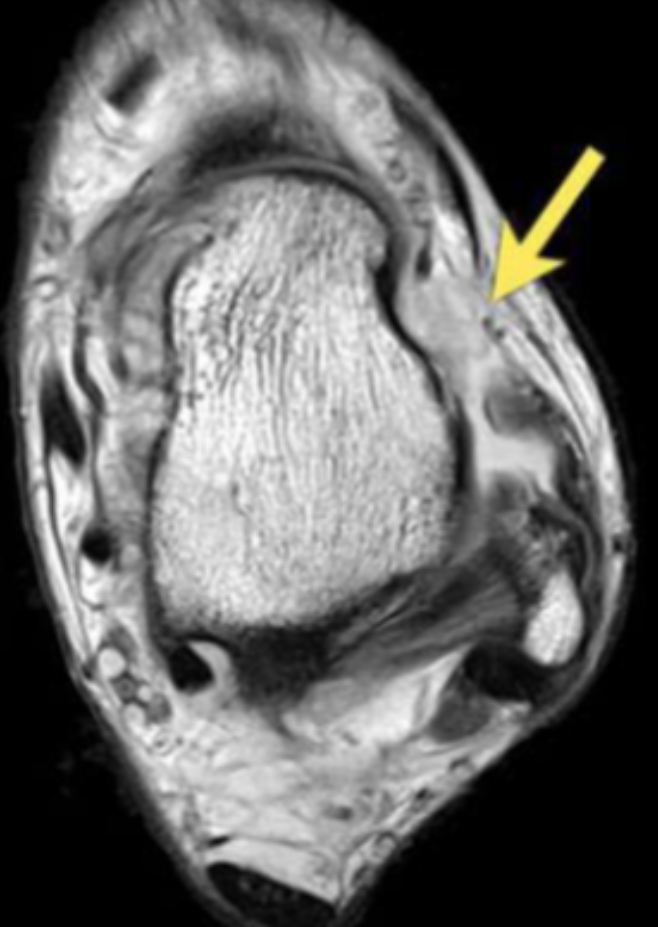

Describe the pathology indicated by the arrow (Ax PD).

Peroneal brevis tendon tear